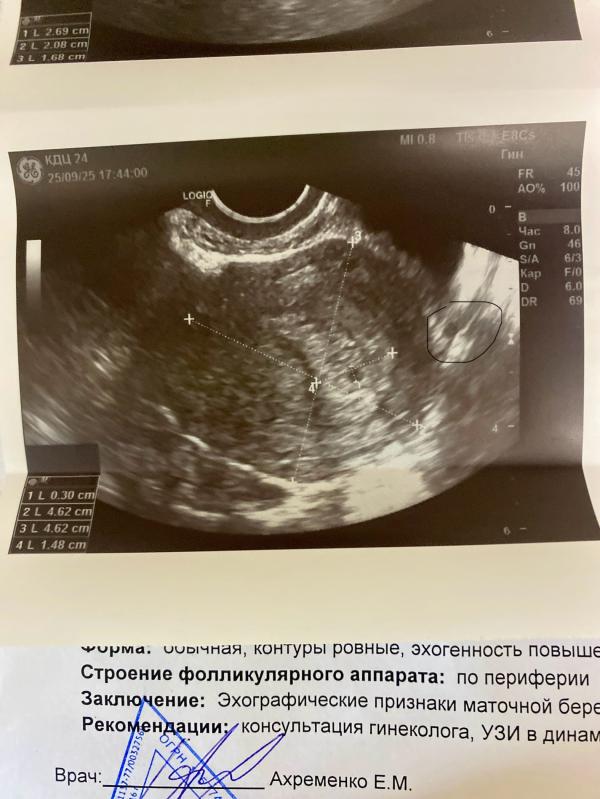

Что это за кружочек рядом с пя? Объясняют мамы

Девочки , а что это еще за 1 кружочек ? Просто похоже как на пя рядом 😂

Это скорей всего часть крупного сосуда попала

То, что отмечено на узи пунктирами - замеры размеров матки. Указанный кружочек - вне ее

Это за пределами матки.